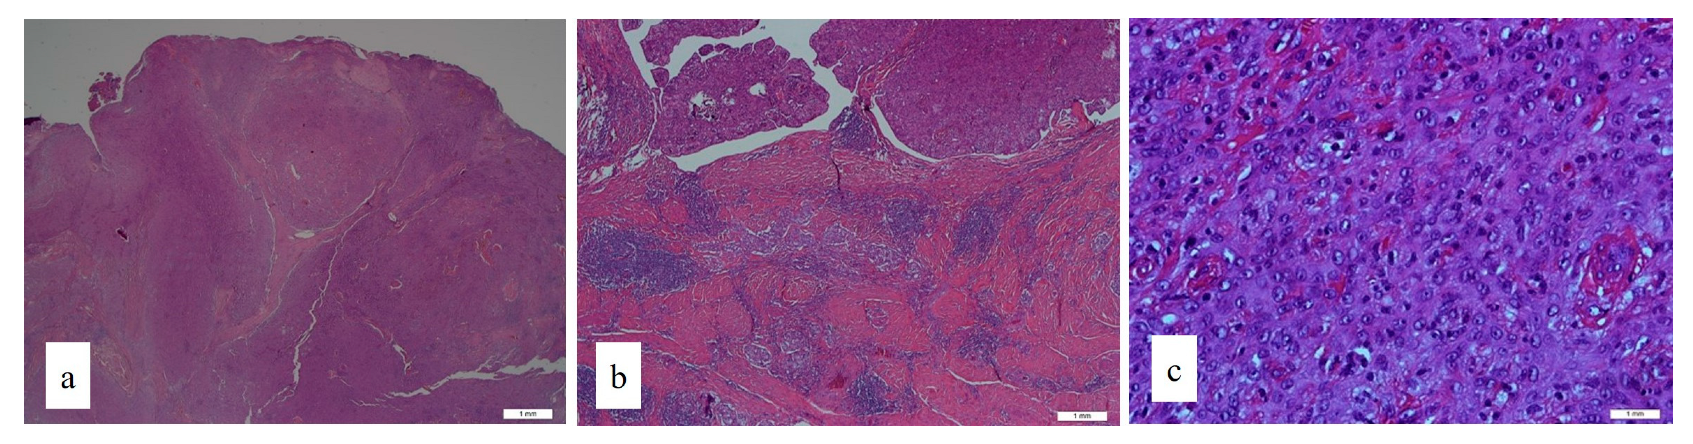

2. Case Report